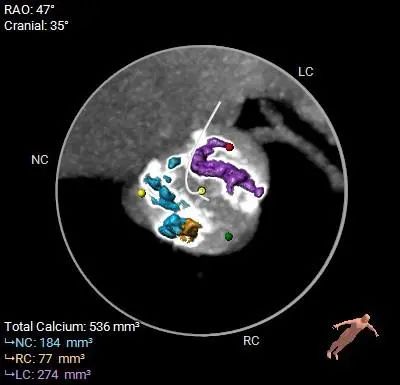

Type 1型二叶式主动脉瓣,右无融合,重度钙化,钙化分布不均匀,无窦和左窦瓣叶钙化较重呈长条块状,右冠窦内钙化向左室流出道衍生,无窦和右窦瓣叶对合缘处存在钙化嵴,左窦和右窦瓣叶对合缘处存在局部钙化黏连,瓣叶对合缘处存在增厚及钙化粘连。

HU850